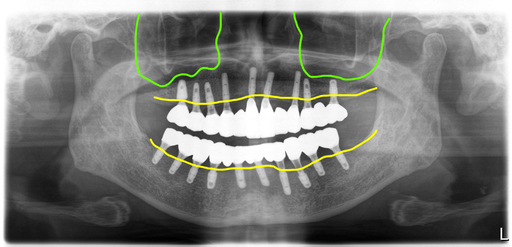

상악에 임플란트주위염이 있는 임플란트와 남은 자연치들을 모두 제거한 후 10개의 임플란트를 식립했고, 아래 전체적으로 흔들리는 보철과 치아들을 제거한 후 임플란트 10개를 식립했습니다.

식립한 임플란트 모두 초기고정이 좋아 바로 지대주를 연결해서 스캔한 후 디자인해서 PMMA로 밀링해서 수술당일 임시치아를 완성해서 세팅해 드렸어요.

대체로 양호한 뼈상태 로 무난하게 최종보철 완성

수술후 4개월 차에 최종보철을 만들기 위한 스캔을 했고 맞춤지대주에 지르코니아 브릿지타입의 보철을 만들어서 완성했어요.

보철은 가능한 너무 뚱뚱하지 않게 만들어서 위생관리에 도움이 되도록 했고, 치간치솔을 사용할 수 있도록 만들었습니다.